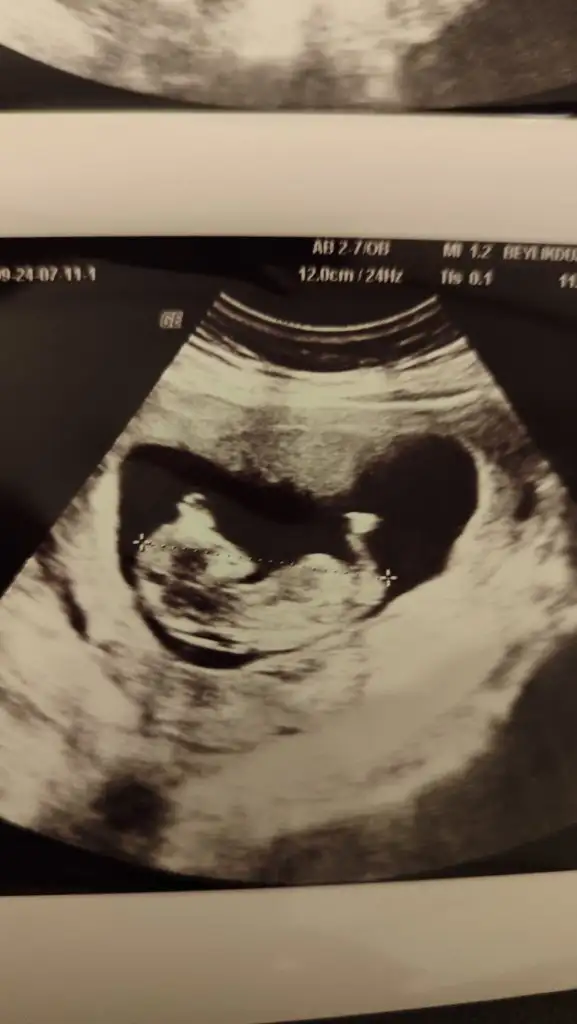

VALAH CANM BEN SAT TARHME GORE10+5 TE OGRENDIM AMA DOKTRMUZ BU DAHA BUYUK 10+5 DEGL DEDI KAYTLARDA 11+5 OLARAK DUZLTTI BU KNTRLMDE BAKICAK DURUMA GORE YINE DEGSTRBLRZ DEDI CUNKU BIZIM FISTIK BAYA NETTİ :)Kızlar aranızda 12+6 iken cinsiyeti öğrenen var mı ben bugün gittim yüzde 80 erkek dedi Dr erken mi acaba